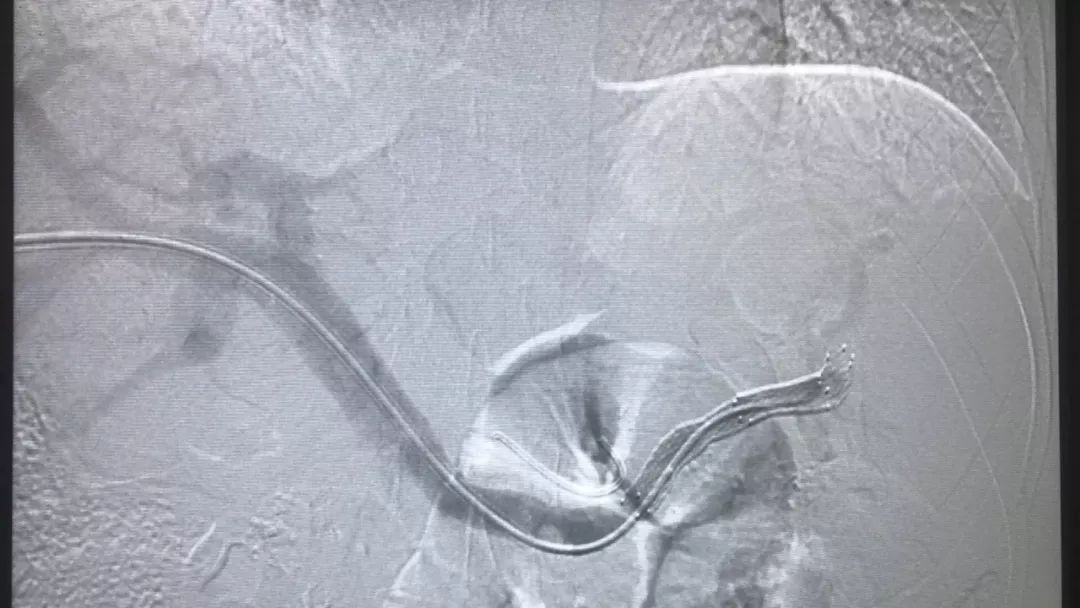

术中造影可见脾静脉闭塞,胃底静脉丛侧枝显影

支架开通后脾静脉通畅,侧枝静脉消失